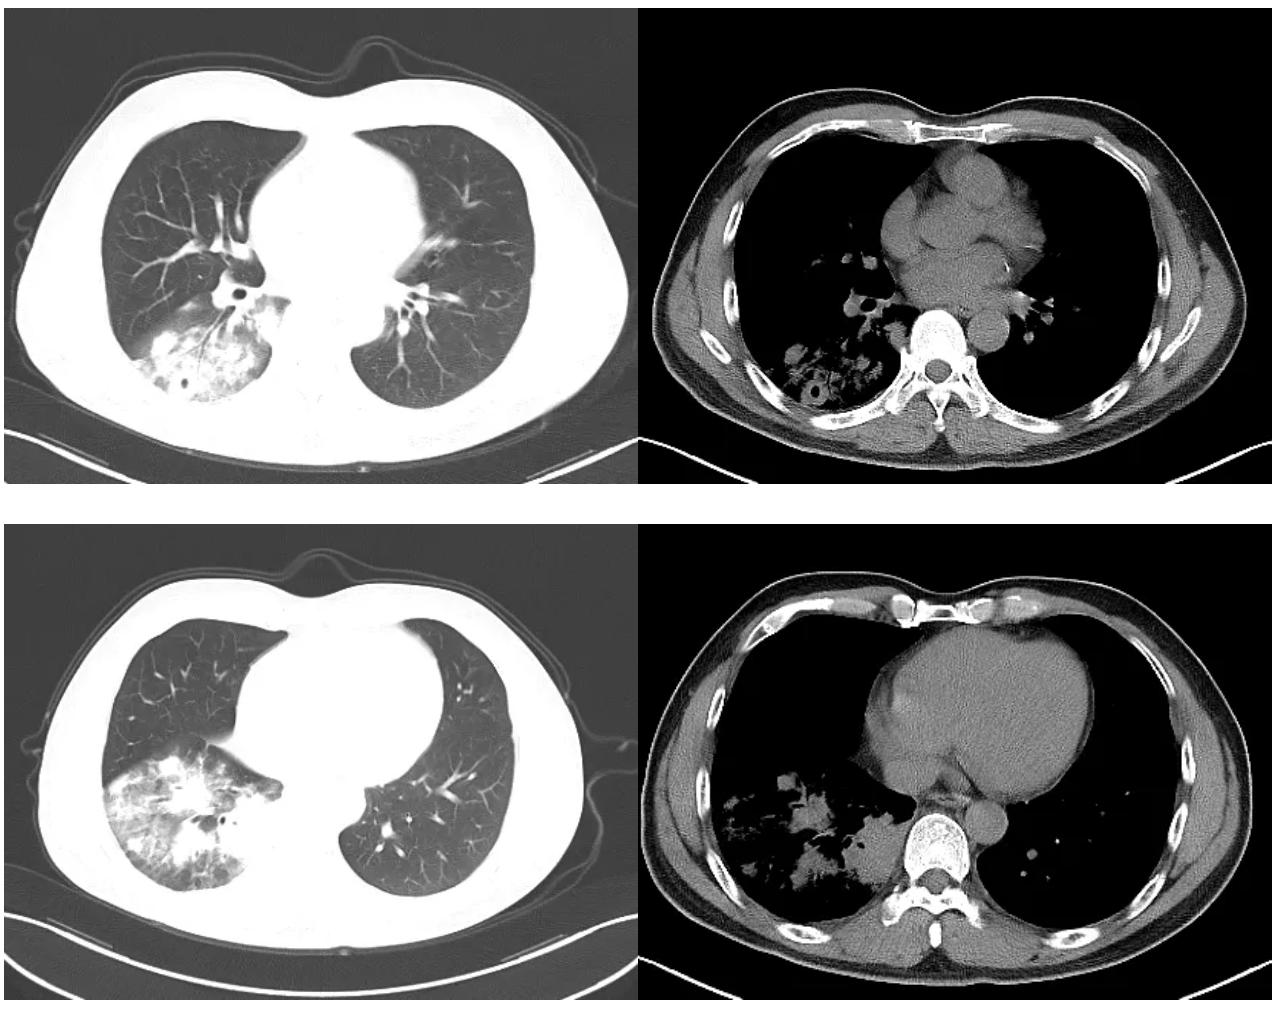

在此阶段,我们修正诊断后,加用了氟康唑400mg/d抗隐球菌治疗。治疗3天后患者咳嗽、胸闷症状出现明显缓解,治疗8天后复查胸部CT示右肺下叶炎症较前稍减轻,右侧少量胸腔积液较前减少(图5)。

图5:氟康唑治疗8天后胸部CT对比,左侧为治疗前,右侧为治疗后